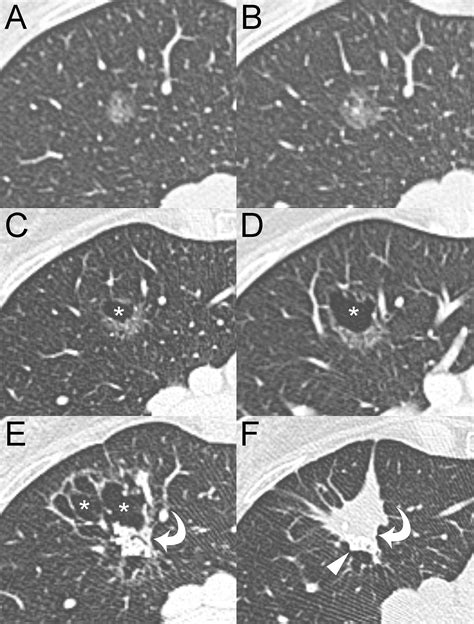

A ground glass nodule (GGN) refers to a hazy, cloudy opacity within the lungs that appears on a CT scan. Unlike solid nodules, which are dense enough to completely obscure the underlying lung tissue, a GGN allows the structures of the lung, such as the airways and blood vessels, to remain visible through the haze. The term derives from the visual similarity to glass that has been treated to appear frosted or translucent.

• Consistency: Whether the nodule is "pure" (completely hazy) or "part-solid" (containing a denser core).

• Persistence: Whether the nodule remains present on follow-up scans performed weeks or months later.

The primary strategy for managing a ground glass nodule is "active surveillance." Because these findings often grow extremely slowly—sometimes over the course of several years—there is rarely a need for immediate, invasive surgery. By performing serial CT scans, your pulmonologist or thoracic surgeon can track changes in size, density, and shape.

While the majority of these nodules are benign or very slow-growing, there are specific "red flags" that may prompt a more aggressive diagnostic approach. If a ground glass nodule begins to develop a larger solid component, or if it shows a rapid increase in size over a short timeframe, your medical team may transition from surveillance to diagnostic testing. This could involve a PET scan to check for metabolic activity or a biopsy to extract a tissue sample for laboratory analysis.